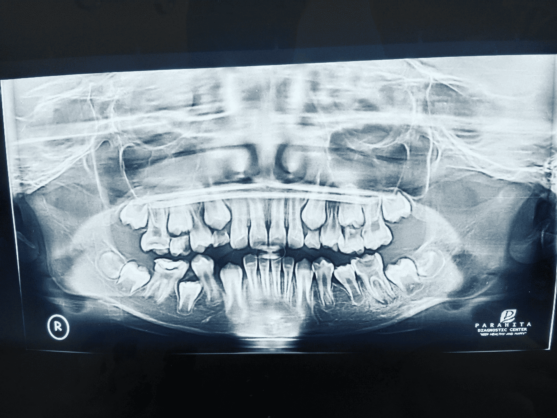

Dalam case report yang dilakukan oleh ketiga dokter spesialis sekaligus dosen FKG Umsida, yakni seorang pasien laki-laki usia 10 tahun mengalami kehilangan gigi 85 (molar sulung bawah kanan) akibat karies parah. Dampaknya, gigi permanen di belakangnya (gigi 46) bergerak ke depan, menyempitkan ruang tumbuh bagi gigi 45 yang belum tumbuh sempurna.

Dalam studi ini, alat dipasang dengan komponen seperti kawat dan pegas terbuka yang diberi tekanan setengah dari panjang aslinya, lalu dicementasi menggunakan semen ionomer kaca.

Hasilnya mencengangkan. Dalam waktu 7 minggu, ruang sebesar 8 mm berhasil dikembalikan, cukup untuk memberi jalan bagi gigi premolar yang sebelumnya terjebak.

Tidak hanya itu, posisi gigi juga berhasil diperbaiki secara vertikal (uprighting), sehingga susunan gigi kembali proporsional.